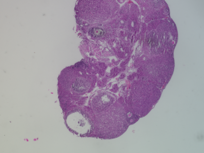

Genus: Mus (mice)

Species: Mus musculus ()

Donor ID: SX_MM_Treatment_5

Life Stage: prepubertal

Age: 0 years, 25 days

Accession #: MDB0000574

Ovary position: unspecified

Location: wholeOvary

Section thickness: 5 microns

Fixation: neutralBufferedFormalin10

Stain: Hematoxylin and Eosin

Immunohistochemistry: None

Experimental treatment: Yes - PFNA, 25 mg/kg, IP injection, 5 days

Other pathology: None